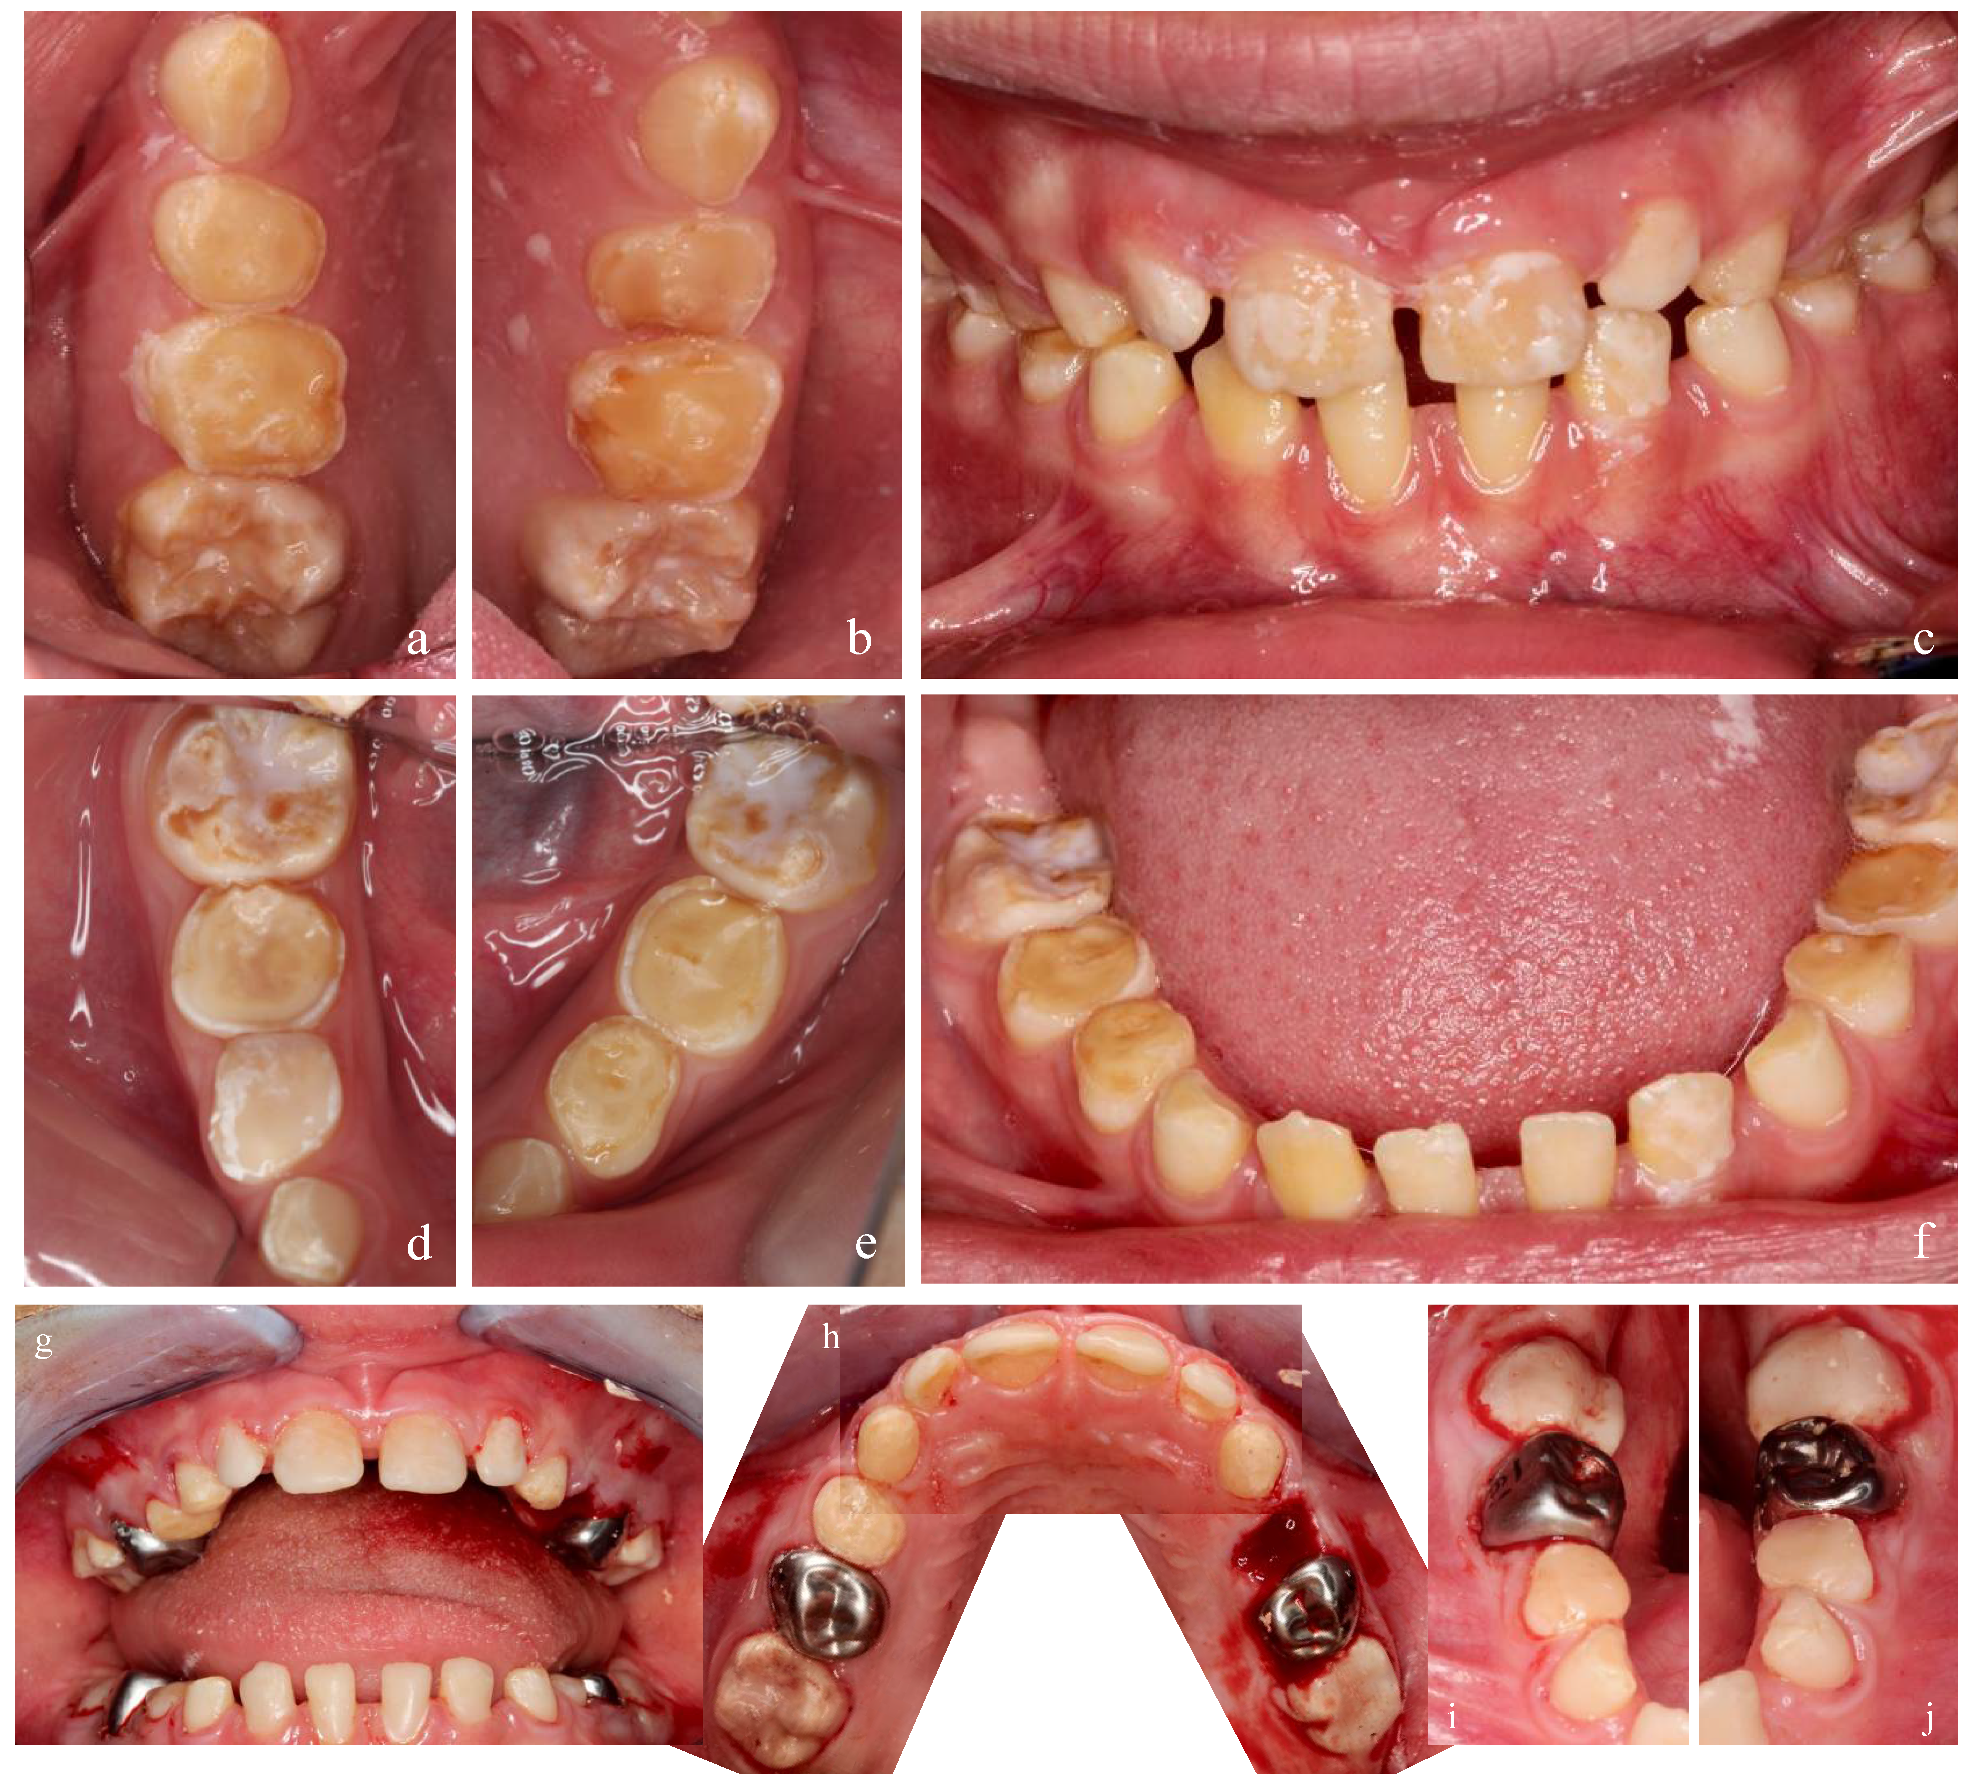

2.1. Case Report 1: Mixed Dentition